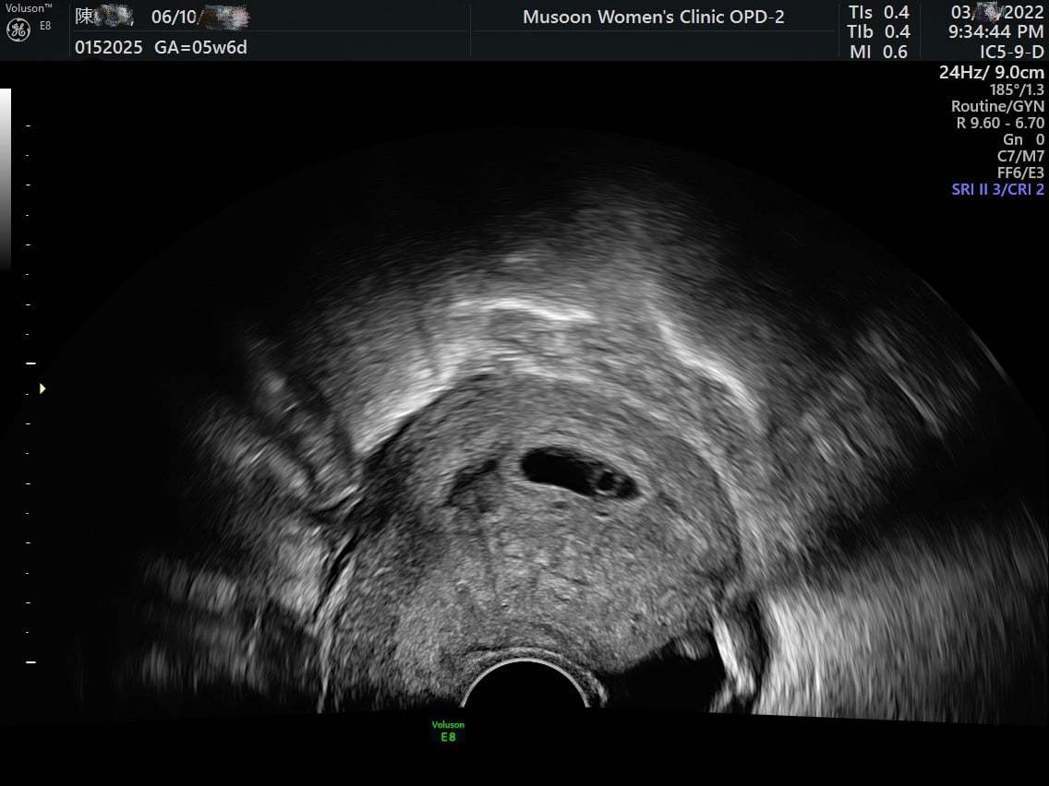

茶花女莉娅(陈缃妮)之前才宣布与谢和弦离婚,不过谢和弦发文开心宣告要当爸爸的喜讯,而随后莉娅也PO出超音波照,证实怀孕的喜讯。茶花女莉娅在去年11月初就曾发文惊吐流产,当时她没有发觉自己怀孕,直到出...

茶花女莉娅(陈缃妮)之前才宣布与谢和弦离婚,不过谢和弦发文开心宣告要当爸爸的喜讯,而随后莉娅也PO出超音波照,证实怀孕的喜讯。

茶花女莉娅在去年11月初就曾发文惊吐流产,当时她没有发觉自己怀孕,直到出现不明出血症状,去医院检查后才发现已怀孕不过已自然流产,网友还酸她「报应」,如今相隔4个月,她发文证实再度怀孕,并心怀感激的写道「谢摇滚回到我们身边了,谢谢大家的关心,感恩的心」。